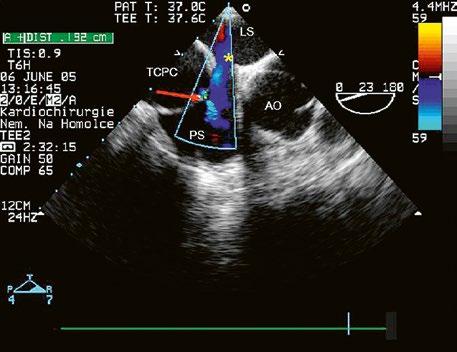

Obr. 45.36 Valvární pulmonální stenóza, doming cípů, jemné cípy, srůst komisur (TEE, longitudinální projekce) AP – kmen plicnice, PK – pravá komora, PS – pravá síň

valvuloplastika, a to bez ohledu na symptomy, při gradientu nad 64 mmHg; u symptomatických pacientů i při nižším gradientu.

Obr. 45.37 Valvární stenóza plicnice, jemná chlopeň, doming cípů, TEE, longitudinální projekce, pacient s transpozičním postavením velkých tepen, aorta (AO) je vepředu, plicnice (AP) vzadu